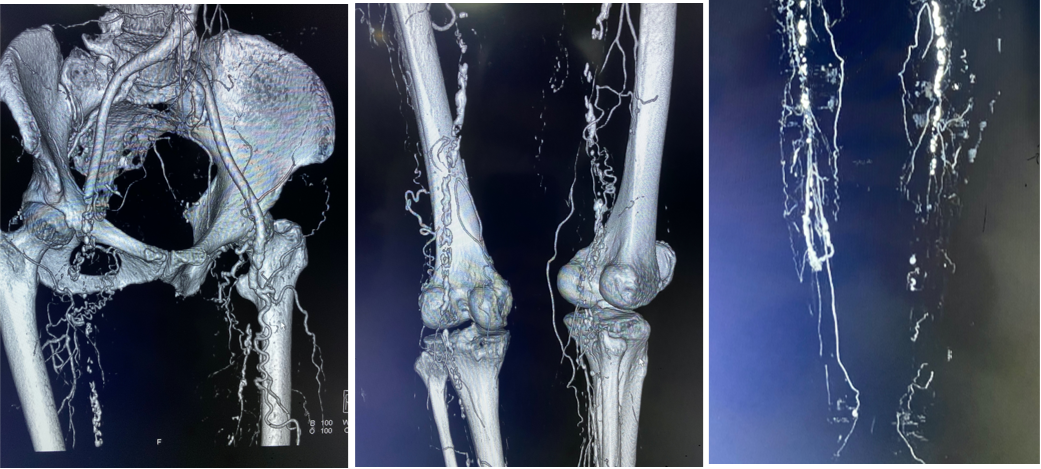

右股总-髂外闭塞,左股-腘动脉全程闭塞,膝下流出道显示不清,重度钙化

图:术前CT

图:造影显示,股腘动脉全程闭塞,膝下流出道差